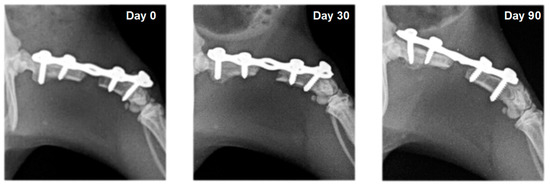

2.4. Radiography

3.2. Radiography